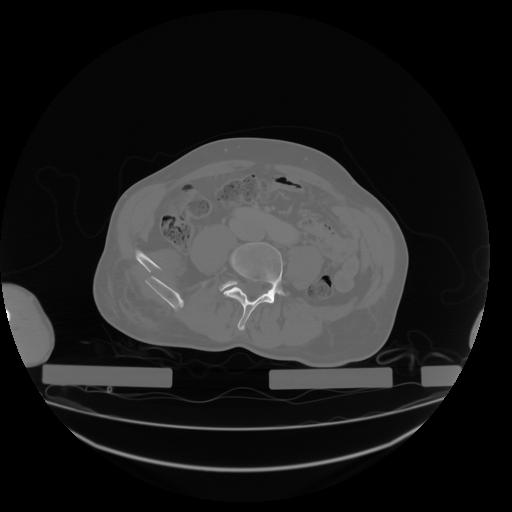

27 CUERPO,CE,Axial,3.0,CUERPO,,